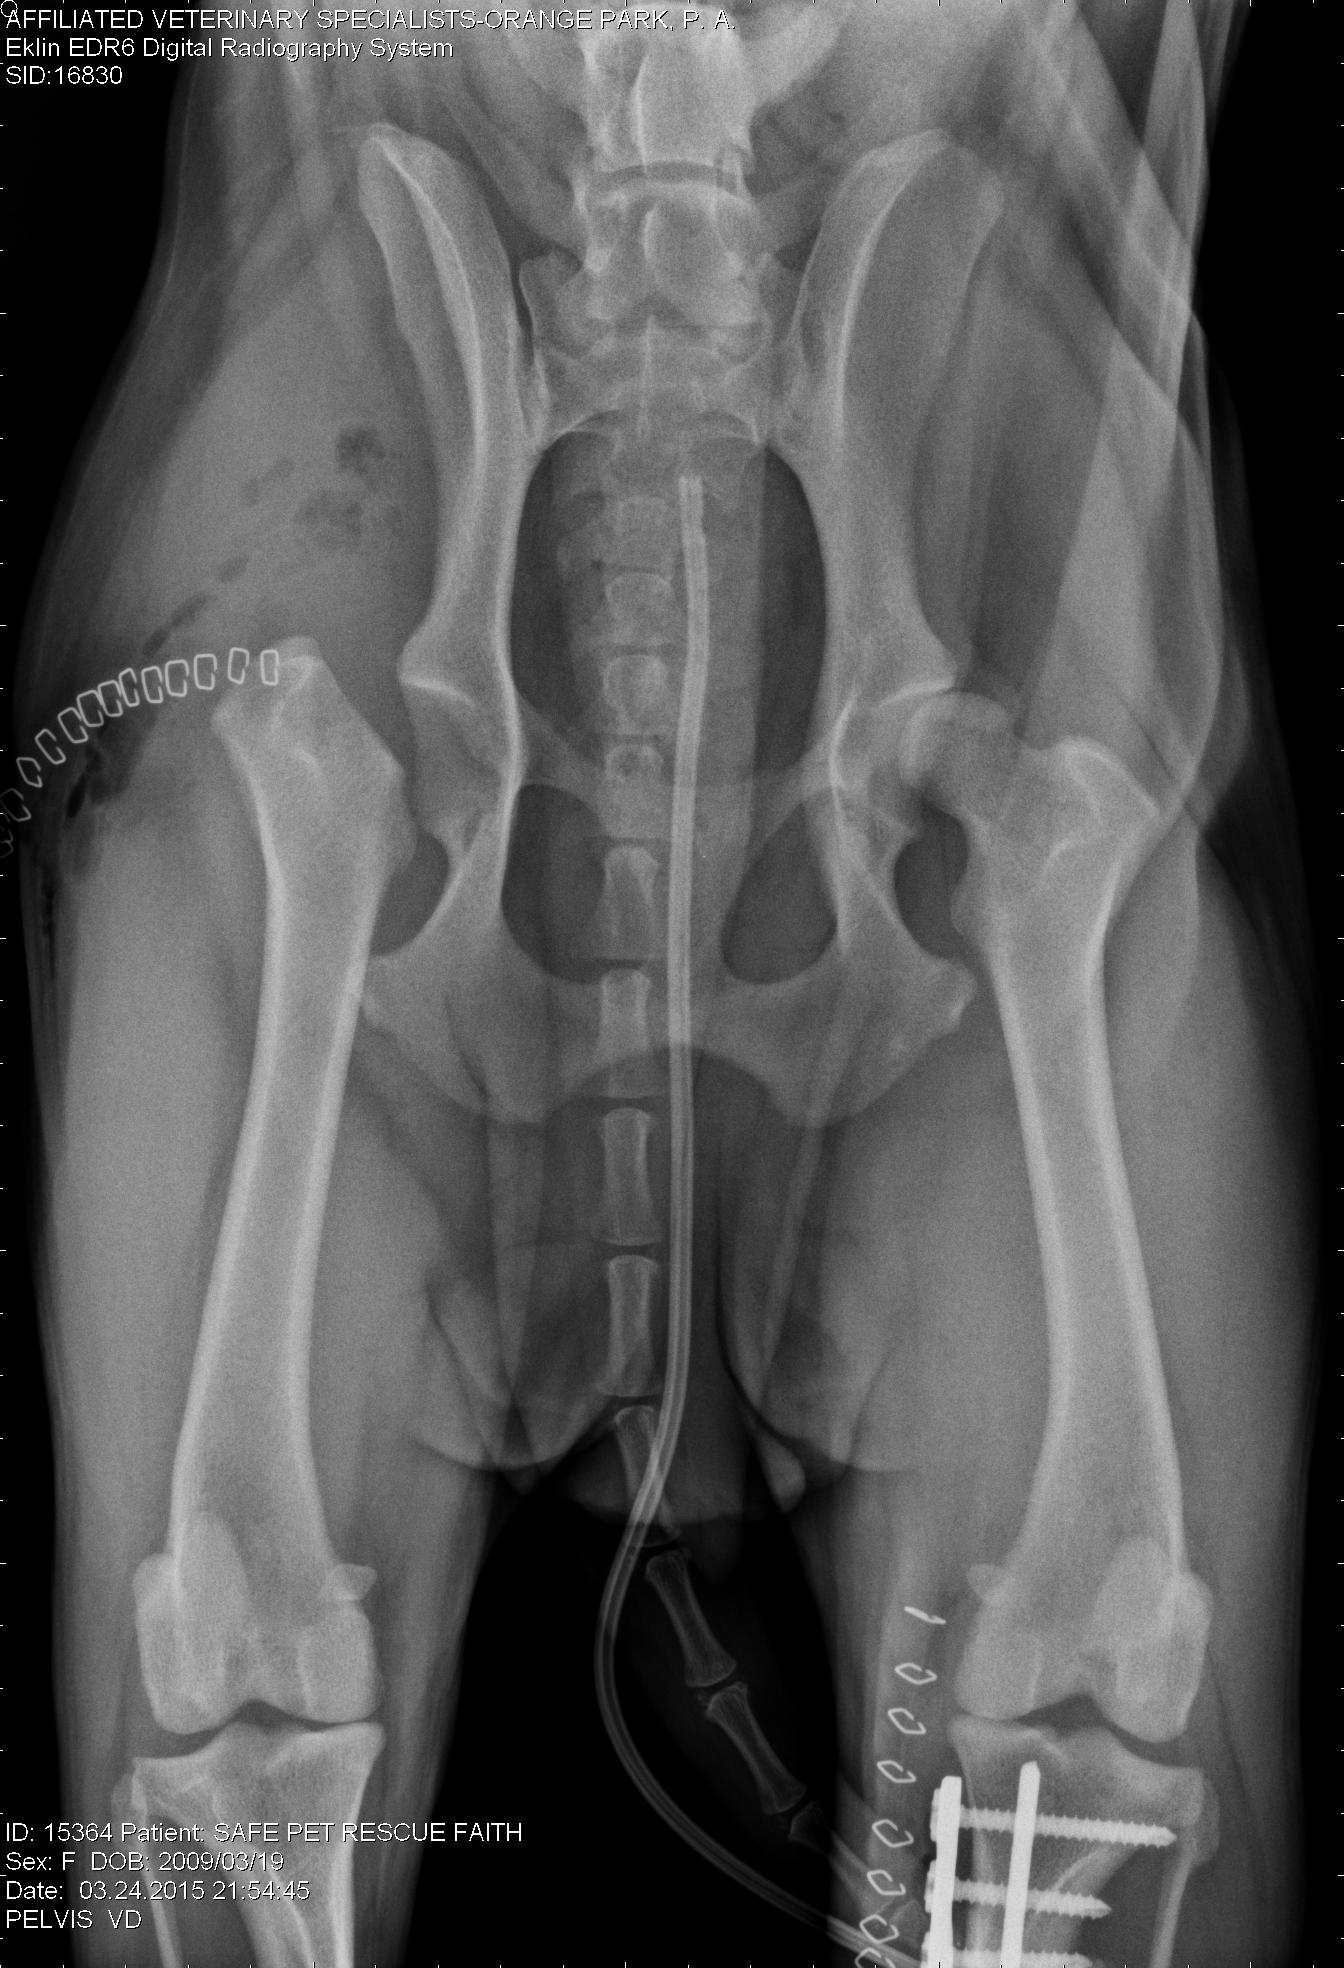

An experienced veterinarian will be able to quickly diagnose this condition, based on signalment (breed), clinical signs, and physical examination. Radiographs (X-rays) generally leave little doubt, as there are “tell-tale” signs seen on x-rays. Blood work will also be performed to assess values such as red blood cell concentration, electrolyte abnormalities, lactate, etc all factors that will be used to guide initial stabilization and treatment prior to surgery. Once diagnosed, surgery is required. If surgery is not feasible (patient is not able to be stabilized, owner unable to move forward with surgery, etc), humane euthanasia will be likely recommended.

This is a right lateral abdominal x-ray. Note the large, dilated stomach and evidence of the duodenum (intestine) just above the stomach and below the spinal column.